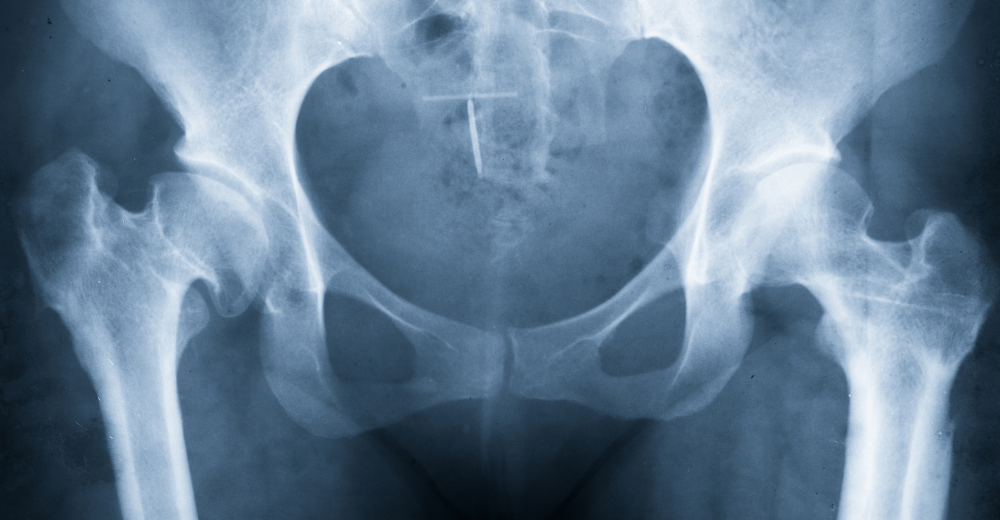

L’Esame RX dell’Anca è cruciale per la diagnosi e la valutazione di diverse patologie legate all’anca. Presso il Poliambulatorio S-Medical Group di Sora, utilizziamo questa tecnologia per identificare condizioni come fratture, osteoartrite e lesioni che possono compromettere la salute dell’anca. Grazie alla nostra meticolosa attenzione e all’esperienza del nostro team, siamo in grado di garantire risultati tempestivi e accurati.

L’Esame RX dell’Anca è una risorsa diagnostica fondamentale per individuare molteplici patologie. Presso il Poliambulatorio S-Medical Group di Sora, utilizziamo questo esame per diagnosticare condizioni come fratture, osteoartrite, displasia e necrosi avascolare. La nostra tecnologia avanzata e l’expertise del nostro team ci permettono di rilevare queste patologie in modo preciso e tempestivo.

L’Esame RX dell’Anca è indicato in diverse circostanze, tra cui:

• Pazienti con dolore persistente all’anca

• Pazienti che hanno subito traumi o lesioni

• Pazienti con sospette fratture

• Pazienti affetti da condizioni croniche come l’osteoartrite

Presso il Poliambulatorio S-Medical Group di Sora, analizziamo ogni caso attentamente e collaboriamo con il paziente per decidere se l’Esame RX dell’Anca sia necessario.